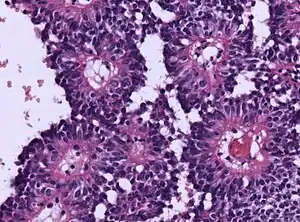

| Micrograph of an astroblastoma showing the characteristic nuclear pervivascular pseudorosette. H&E stain. | |